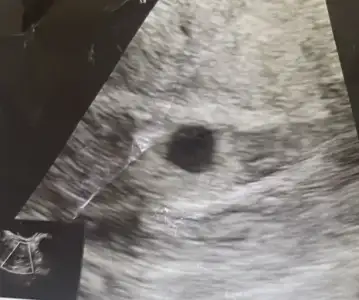

Son adet tarihim 1 eylül, 10 eylülde çatlatma iğnesi oldum. 25 eylülde 52 betayla öğrendim 2 gün sonra 87 oldu 3 gün sonra 91 de kaldı sonra düzenli arttı 1 hafta sonra kese oluşumu gördük sonraki hafta 15 ekimde tam 5 haftamın başında 7 mm kese gözüktü 22 ekimde 6 haftamın başında gittim kese sadece 1 mm büyümüş dedi sağlıksız mı kesin, geç döllenme olabilir mi ? kafam allak bullak ağrım, akıntım lekelenme yok. Yaşayan var mı bunu kesemin şekli düzgün bozulma vs yok ama kalp atısı vs hic biseyde gözükmedi